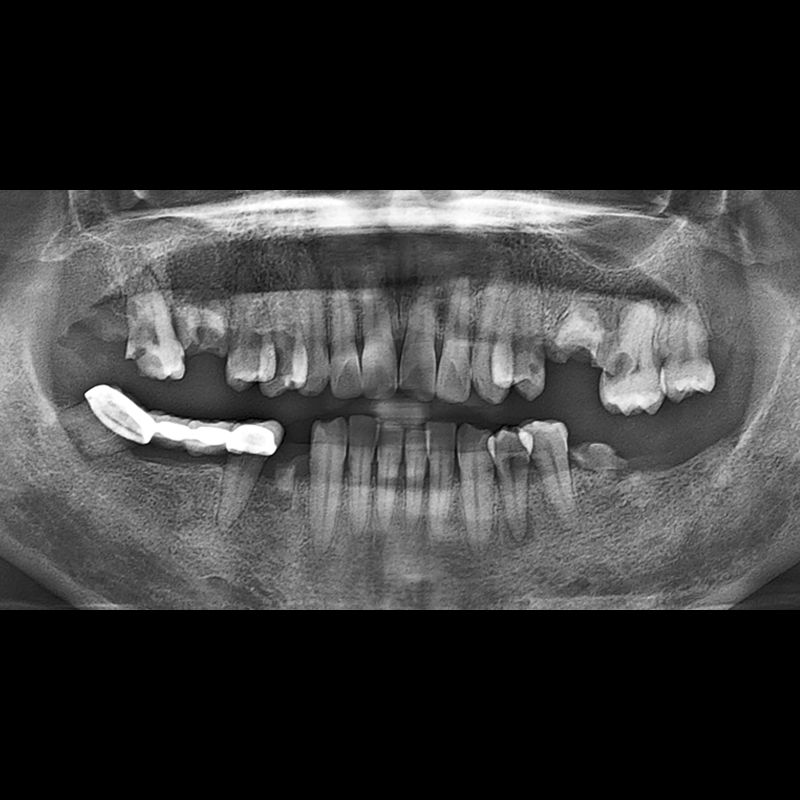

种植牙前后的照片 2025.12.10

在缺失的牙齿部分和难以挽救的牙齿位置植入了种植牙。